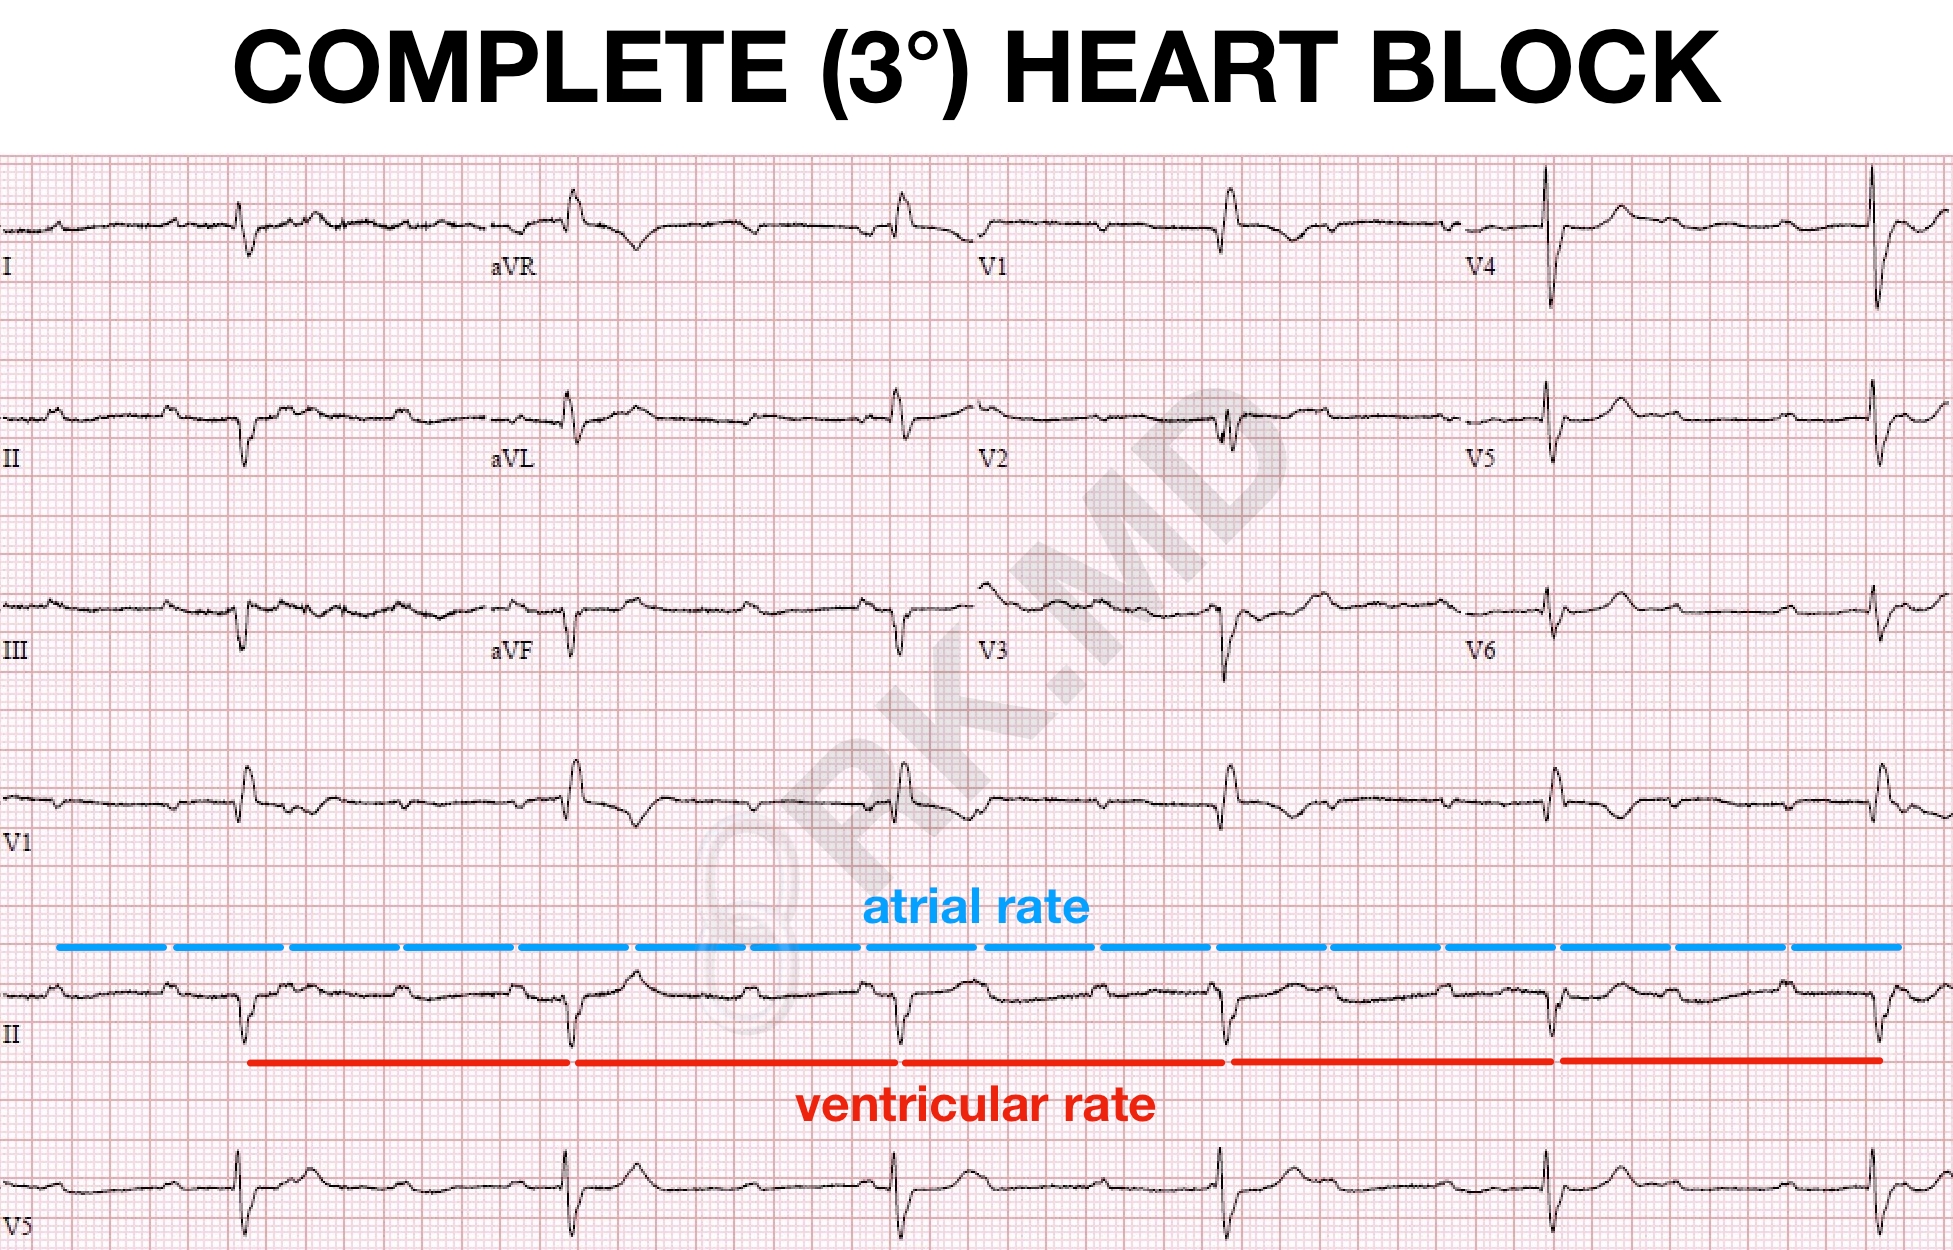

Complete 3 Heart Block EKG RK MD

Cardiac Muscle And Electrical Activity Nursing Mnemonics Nurse Icu

Cardiac Muscle And Electrical Activity Nursing Mnemonics Nurse Icu